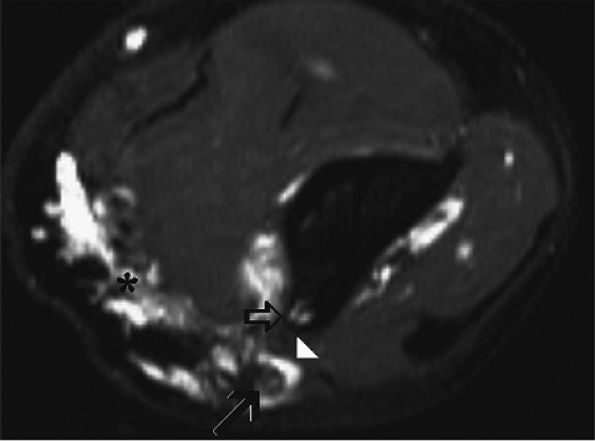

FIGURE 12.19 ● Ulnar neuropathy secondary to compression by hemangioma. An axial post-gadolinium fat-suppressed T1-weighted image shows an avidly enhancing soft-tissue mass encasing (arrowhead) the ulnar nerve (solid arrow) in the medial aspect of the distal arm, consistent with a hemangioma (asterisk). Note invasion of the medial humerus by the mass (open arrow).

|

FIGURE 12.20 ● Ulnar neurop-athy secondary to scar. Axial T1-weighted (A) and fat-suppressed T2-weighted (B) images demonstrate encasement of the ulnar nerve (arrowhead) by scar tissue (arrows). Selective denervation edema of the flexor carpi ulnaris (fcu) muscle in the proximal forearm is noted.